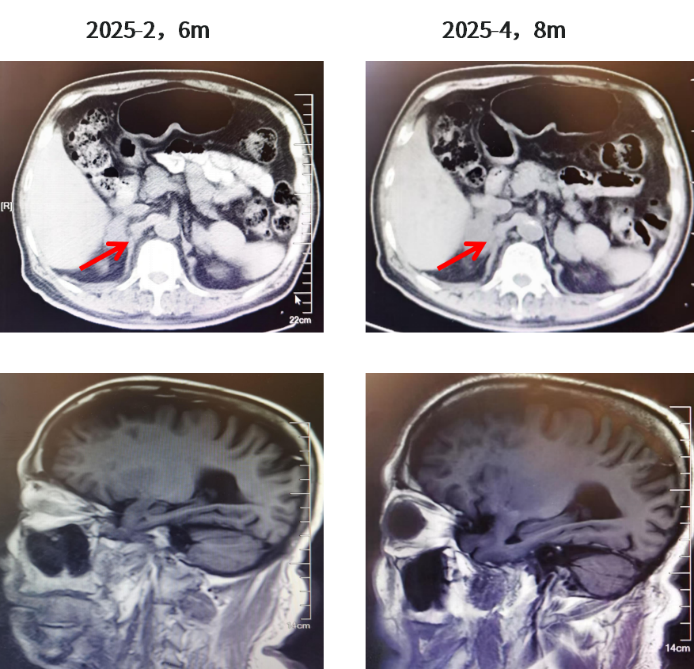

靶向药物建议调整为一线伏美替尼80mg QD 联合伯瑞替尼100mg BID 靶向治疗(伯瑞替尼建议QD增加为BID);但患者高龄,且未出现肾上腺进展后的不良反应,仍自行继续伏美替尼80mg QD+伯瑞替尼100mg QD口服靶向治疗。2025年4月,肿瘤标志物继续增高(CYFRA21-1升至6.89,CA19-9升至293.6)。

图6. 胸部CT(2025.02、2025.04)

图7.肾上腺CT结果及颅脑MR结果(2025.02、2025.04)